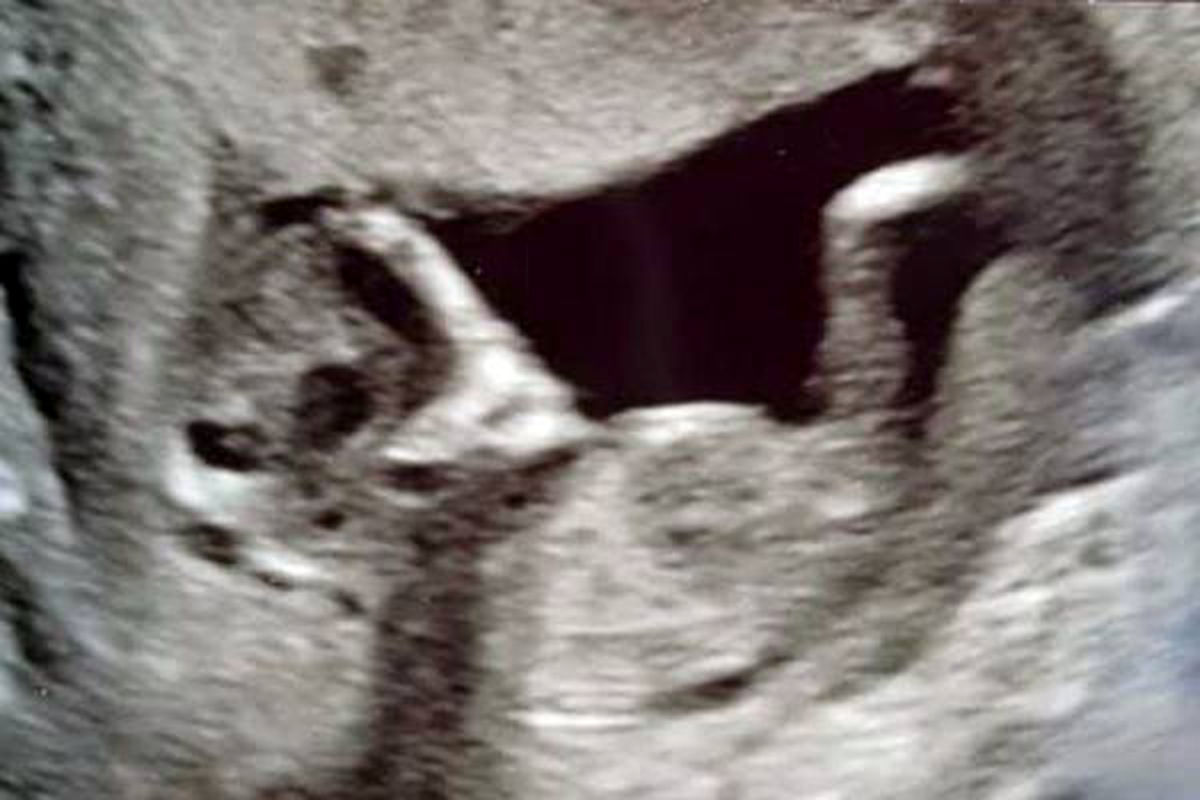

سونوگرافی ترسناک یک زوج انگلیسی در فضای مجازی خبرساز شد.

چشم‌های موجودات فضایی در رحم مادر جوان انگلیسی سوژه رسانه‌ها شد.

ماجرا از آن قرار است که مادری جوان در انگلیس در سونوگرافی اخیرش با صحنه‌ای عجیب و ترسناک در رحمش مواجه شد که تصمیم گرفت آن را در فضای مجازی انتشار دهد.

سوفی اسکات ۱۶ ساله و استیفن ۲۴ ساله زمانی که برای سونوگرافی به پیش پزشک رفتند با صحنه‌ای عجیب در شکم سوفی مواجه شدند که آن‌ها را تاحدودی ترساند.

در شکم سوفی دو چشم عجیب و ترسناک جنین به چشم می‌خورد که به شدت به موجودات فضایی شباهت دارد به همین منظور موجب ترس و وحشت آن‌ها شده است.

به گفته سوفی: من ترسیدم که این موجود بیگانه جنین من را خورده باشد و این چشمان چشم‌های یک موجود فضایی به جای دخترم در شکمم باشد.